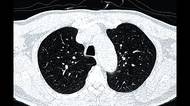

Nebezpečná Paracetamolová výzva (Paracetamol challenge) se šíří prostřednictvím sociálních sítí a zahrnuje intoxikaci pomocí nepřiměřené dávky paracetamolu a následné online sdílení jednotlivých kroků výzvy (požití dávky, poskytování přednemocniční neodkladné péče, transport do zdravotnického zařízení a následnou hospitalizaci dotčeného jedince). Proto se zde věnujeme intoxikaci paracetamolem, včetně jejích rizik, je zde charakteristika postupů poskytnutí přednemocniční neodkladné péče a nemocniční péče. A rovněž je poukázáno na nebezpečí související se závislostí na sociálních sítích.